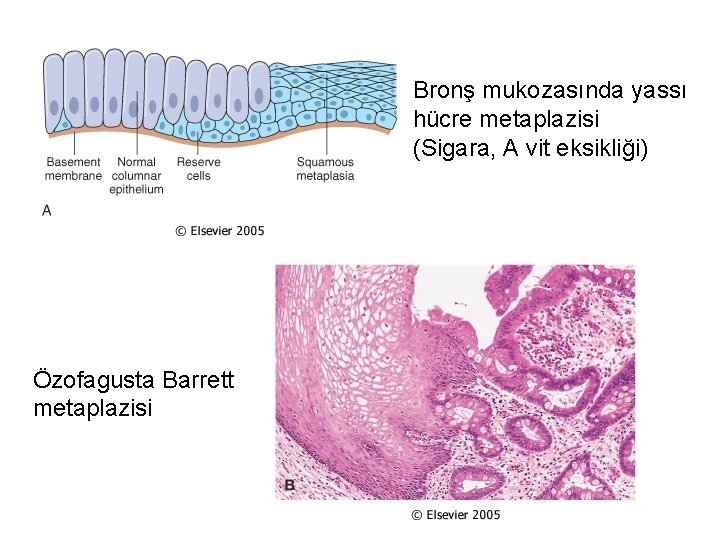

Bronş mukozasında yassı hücre metaplazisi (Sigara, A vit eksikliği) Özofagusta Barrett metaplazisi